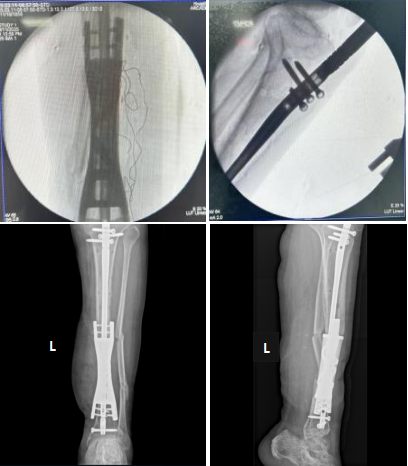

图5. 术中影像

术后影像

图6. 术后正侧位片